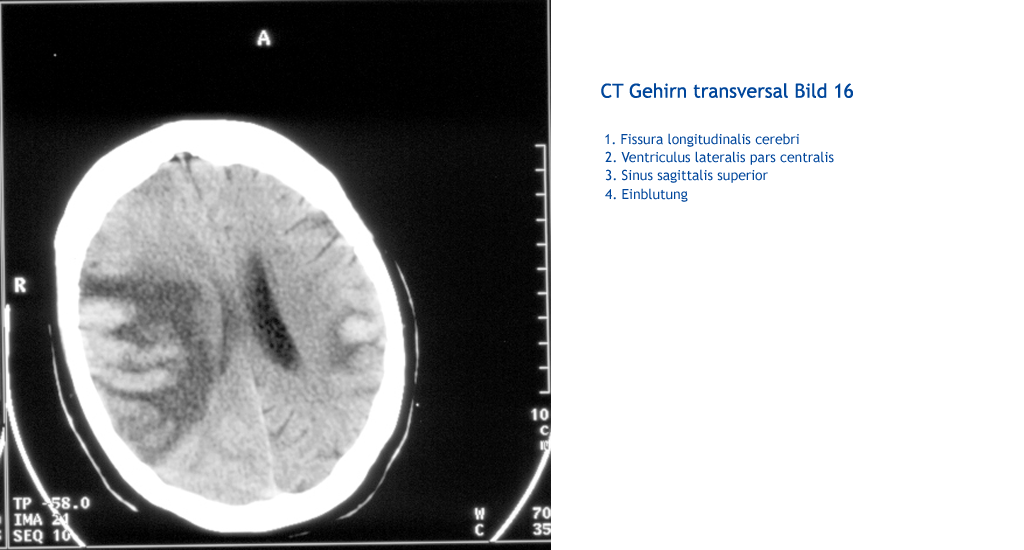

Einblutung Sinus sagittalis superior Sinus sagittalis superior Ventriculus lateralis pars centralis Fissura longitudinalis cerebri